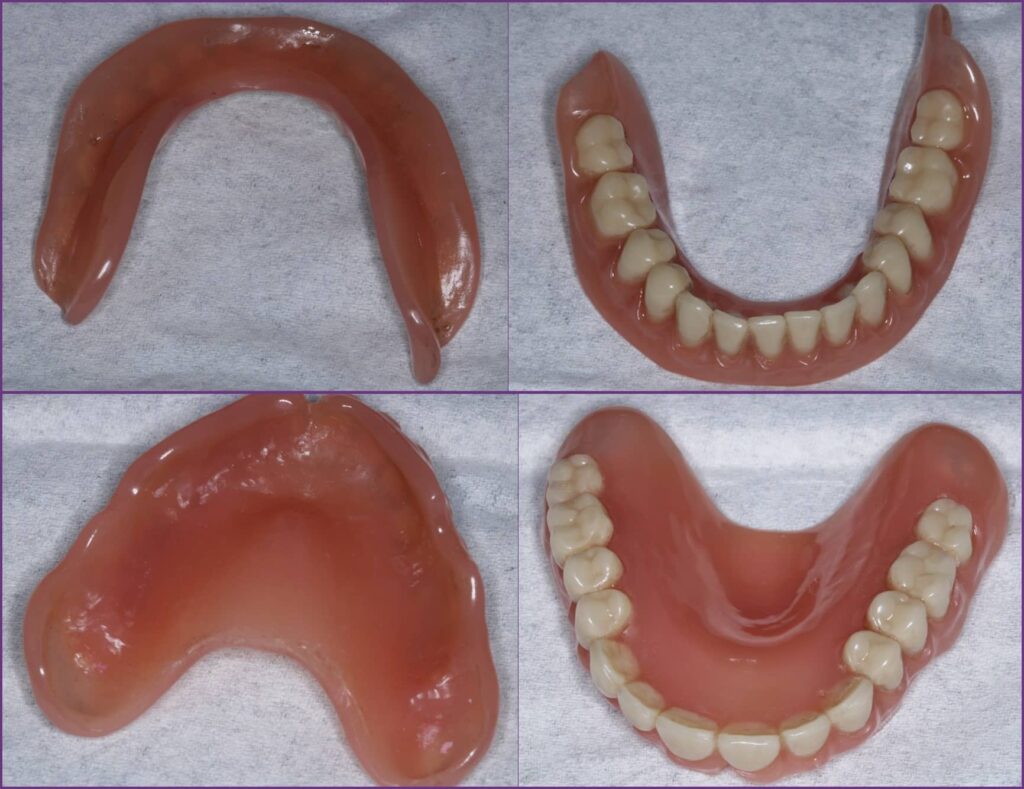

Az átadás során átadásra került az alsó fogpótlás nyálkahártya felé tekintő része, az alsó fogpótlás szájüreg felé tekintő felszíne, a felső fogpótlás nyálkahártya felé tekintő része és a felső fogpótlás szájüreg felé tekintő felszíne.

Fogpótlás teljes lemezes átadás